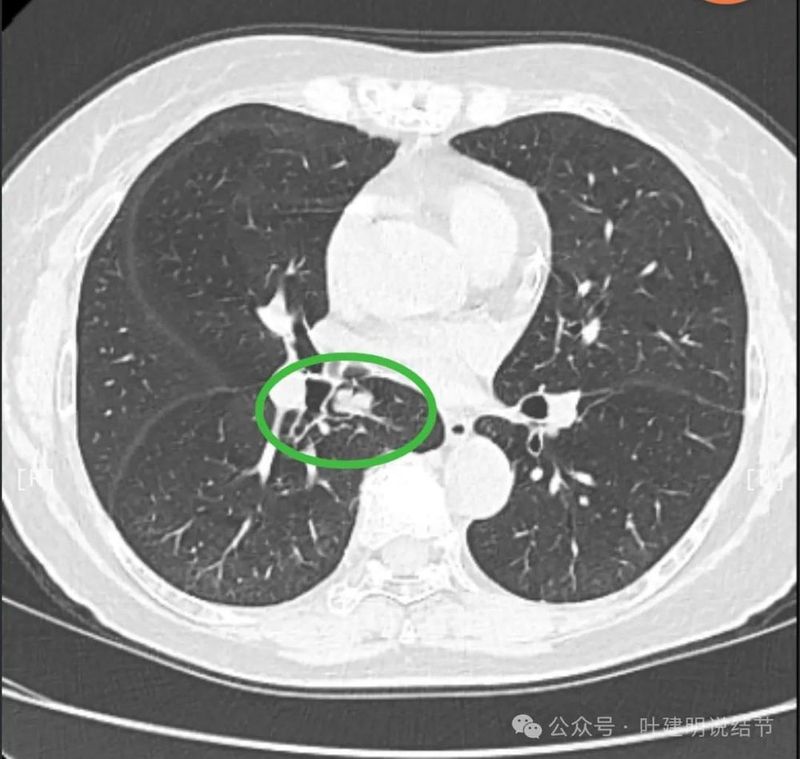

再看2024年5月时复查的影像:

分叶,混合偏实性密度,血管贴边走行。

与支气管紧贴,黄色箭头所示处似乎支气管壁与病灶已经愈着。

上图又见结节与支气管不是都愈着的,说明侵袭性并不强,病灶表面光滑。

天蓝色箭头所指处是北段支气管与病灶之间,感觉较2月份贴得近了一点点。病灶表面仍是光滑的,总体感觉有膨胀性。

病灶边缘光滑,有血管穿出来似的。

表面光滑,有膨胀性。

内部密度较为均匀,就位于肺门部。

边缘光滑,实性,有膨胀感。

与血管关系近。

边缘区域与下肺静脉间隙不太清楚。